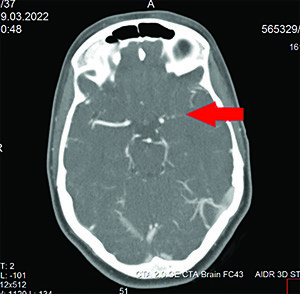

Рисунок 1. Результат проведения КТ-ангиографии: окклюзия левой ВСА до М1-сегмента.На КТ ГМ: патологических объемных образований головного мозга не выявлено. Денситометрические показатели вещества головного мозга соответствуют нормальным величинам. Желудочки мозга, кортикальные борозды, базальные цистерны обычных размеров. Срединные структуры не смещены. Турецкое седло обычной формы, размеров.

При выполнении КТ-ангиографии головного мозга выявлена окклюзия левой ВСА до М1-сегмента (см. рис. 1).